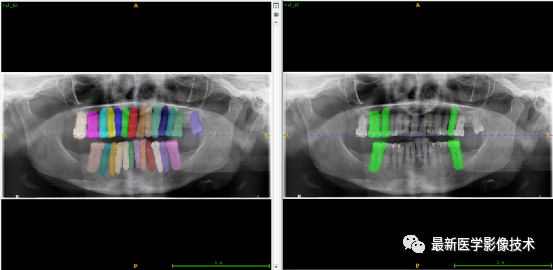

验证集牙齿分割计数和异常牙齿分割识别

左图是分割计数,右图是异常牙齿分割识别结果